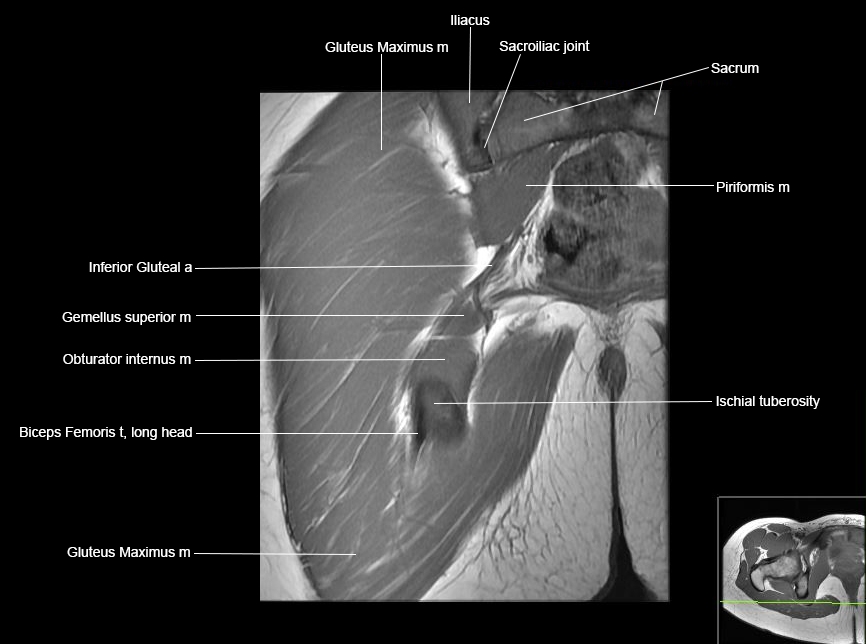

MRI Hip Anatomy

Scroll using the mouse wheel or the arrows